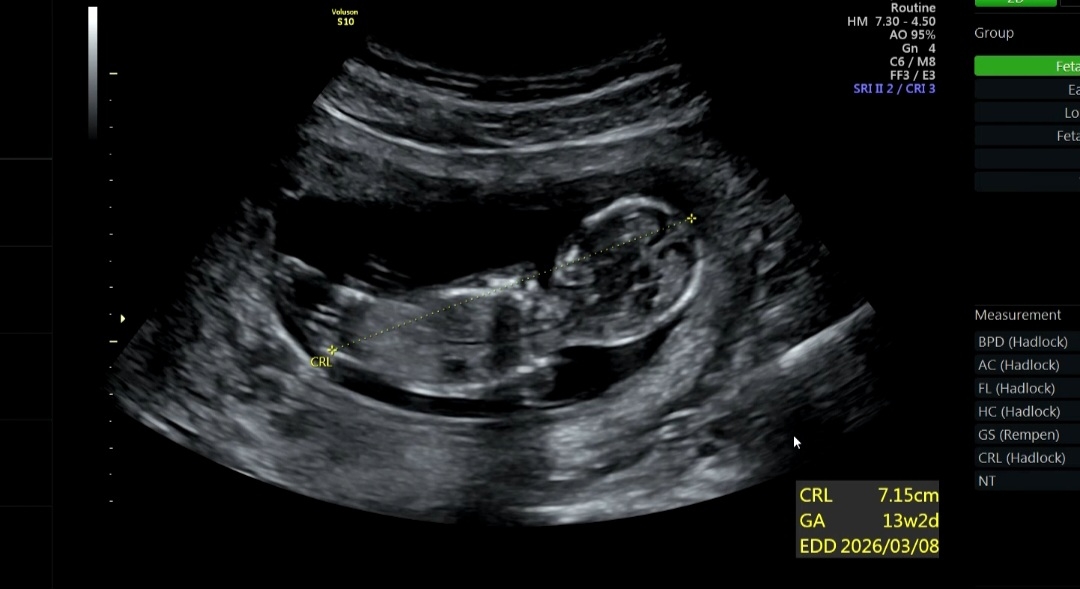

2026년 3월 베동

각도법 보일까요?

12주차 3일 입니다:) 남편이랑 저는 봐도 모르겠어서 글 올려봐요! 딸일까요? 아들일까요?